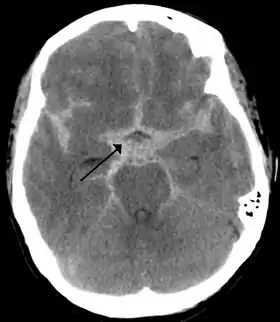

![]() تصوير أشعة مقطعية يظهر نزف تحت العنكبوتية كمنطقة بيضاء في الوسط وتمتد إلى الأتلام في كلا الجانبين (انظر السهم) تصوير أشعة مقطعية يظهر نزف تحت العنكبوتية كمنطقة بيضاء في الوسط وتمتد إلى الأتلام في كلا الجانبين (انظر السهم) | |